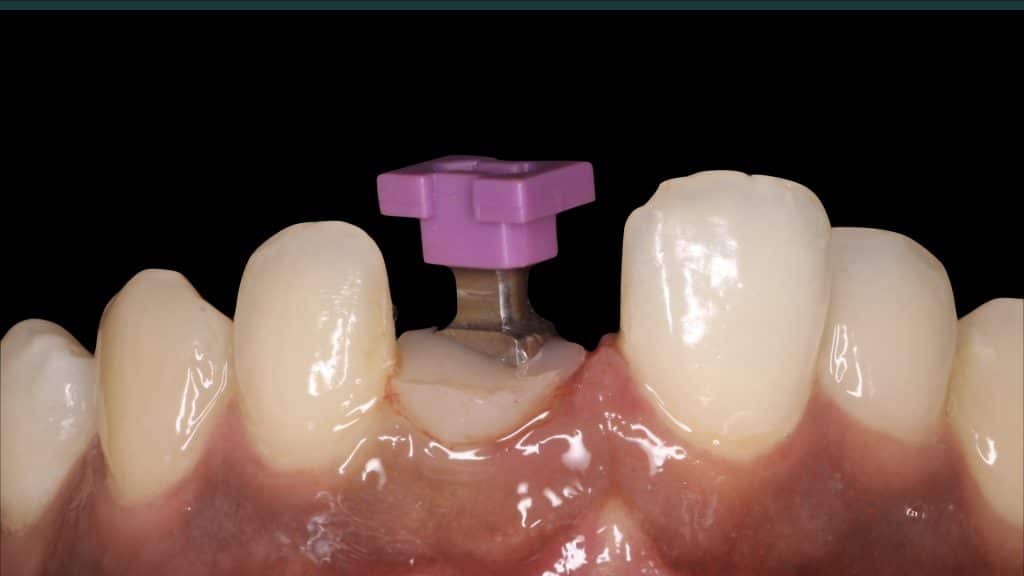

Occlusal check